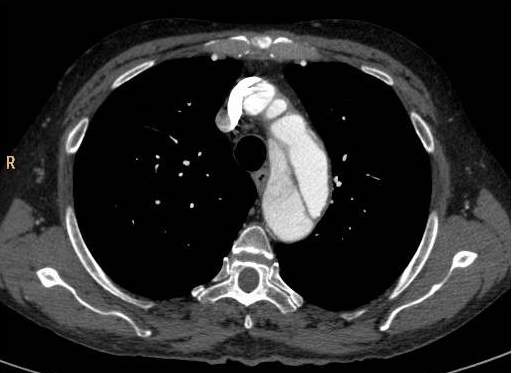

Image

Saddle embolus is blocking both branches of the pulmonary trunk

Bilateral, multiplex emboli in the hilar branches

Fig. 9., 10.: CT angiography examination of acute pulmonary embolisation